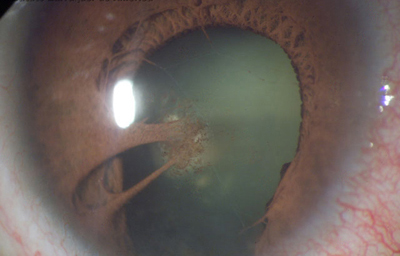

Aniridia completa, catarata y distrofia corneal de la aniridia

Archivo Dr. Francisco Barraquer

Síndrome de Peters. Descrita por Albert Hans Peters (1862-1938) en 1906. Se caracteriza por ser una anormalidad en la que existe una opacidad corneal central, con ausencia de membrana de Descemet y Endotelio en la zona de la opacidad y adherencias iridocorneales con patrón variable a la zona corneal afectada; muchos casos se asocian con Glaucoma congénito, Aniridia y Microcórnea. Se considera que pudo existir un retraso en la separación del cristalino de la placa ectodermica superficial que le dio origen. En el S. de Peters se describen tipo 1, el tipo 2 y el tipo Peters Plus, en el cual existen alteraciones en el cristalino, tiende a ser bilateral y se asocia con anormalidades sistémicas como retraso del desarrollo, defectos cardiovasculares, mala audición, defectos en el sistema nervioso central, defectos genitourinarios y gastrointestinales.

El compromiso corneal lo diferencia del Síndrome de Axenfeld-Rieger

Sindrome de Peters

Archivo fotográfico Dr. Carmen Barraquer

Sindrome de Peters

Archivo fotográfico Dr. Carmen Barraquer